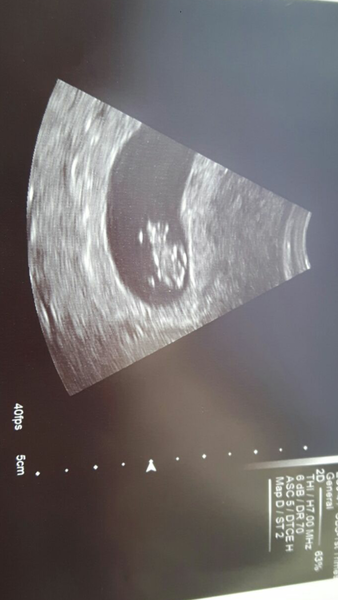

We had a scan yesterday, 8+2 and all looked well :)

How lovely to see a scan :) I basically feel hungover. But I go from feeling awful to feeling fine within minutes. I'm usually hungry in the evening but dinner is cooking and I don't much fancy it tonight. However if McDonalds was on offer that would be a whole different story. I was hooked on fast food last time as well.

Lovely pic PupPup!

Lovely pic PupPup No Facebook group yet I think. Set one up?

Cute scan pup hello baby!

Lovely scan pic pup Smile